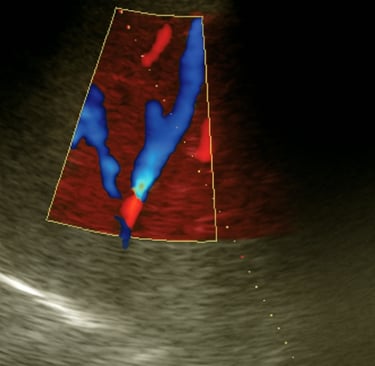

Ultrasonografía del cuadrante superior derecho para identificar vena hepática media o derecha permeable

Ecografía de la vena hepática media

Venografía por punción transhepática eco-guiada